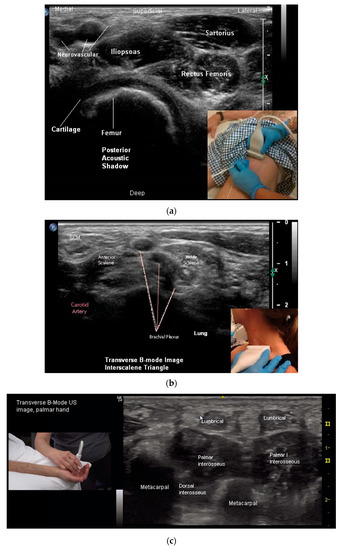

While muscles can be imaged in either transvers or longitudinal view, muscle pattern recognition is best obtained in the transverse view [24] (Figure 1a,b, Figure 5a–d, Figure 6a–c and Figure 7a,b). Features that are better appreciated in the transverse view muscles include muscle contour lines and adjacent muscles, bones, vessels, nerves and other structures [24,45,49,53] (Figure 1a and Figure 5a–d).

Figure 5.

(a) Transverse B-mode US image, Proximal Thigh; (b) transverse B-mode US image, Interscalene Triangle; (c) transverse B-mode US Image, hand (palmar view); (d) transverse B-mode US image, posterior calf (Distal 1/3).